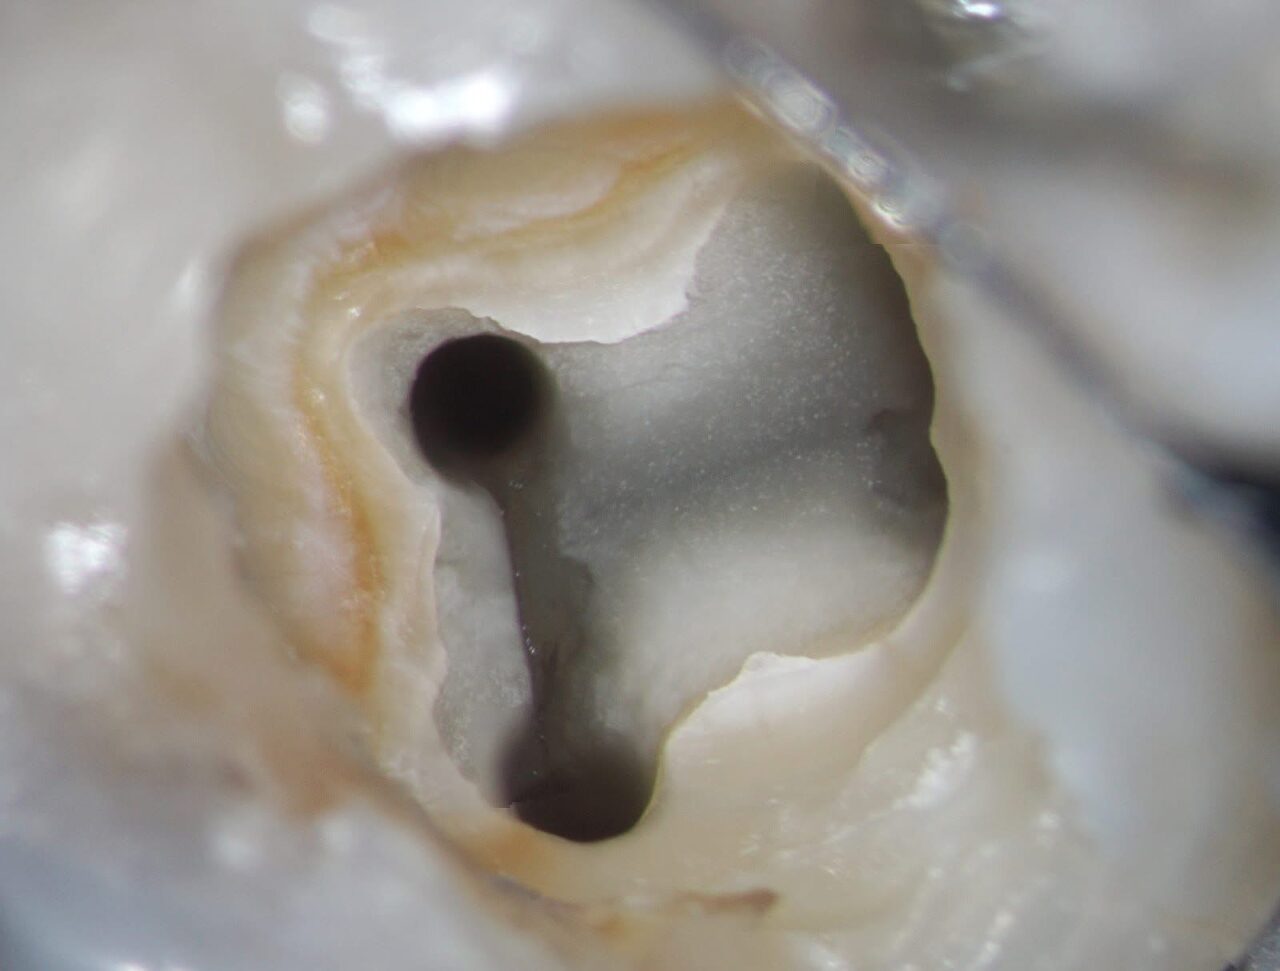

根管拡大及び根管洗浄後の写真です。